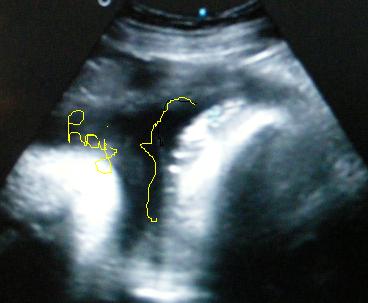

Minden rendben lurkóval, valóban fejvégű, 2100 gr. Kissé nagyobb lesz, mint Bátyja. Megint szóba jött a doki-dolog, hát eléggé meglepődött, amikor mondtam, hogy valószínűleg a dokim nézte el a gyerek fekvését (26. héten faros volt, utána éreztem egy fordulást -egyértelműen-, 30. héten mégis farosnak mondta a doki, azaóta nem éreztem fordulást és most viszont fejvégű (meg ugye előző héten is az volt) ergo szerintem a doki nézte el. No a lényeg, hogy megint beszéltünk erről, de mondtam Neki, hogy már nem akarok nagyon ugrálni... Amúgy a szülésznőmnek mondta, hogy majd együtt szülnek és hogy én leszek az... jééé emlékszik... És lenne mégegy téma ezzel kapcsolatban, de azt nem merem itt nyíltan...